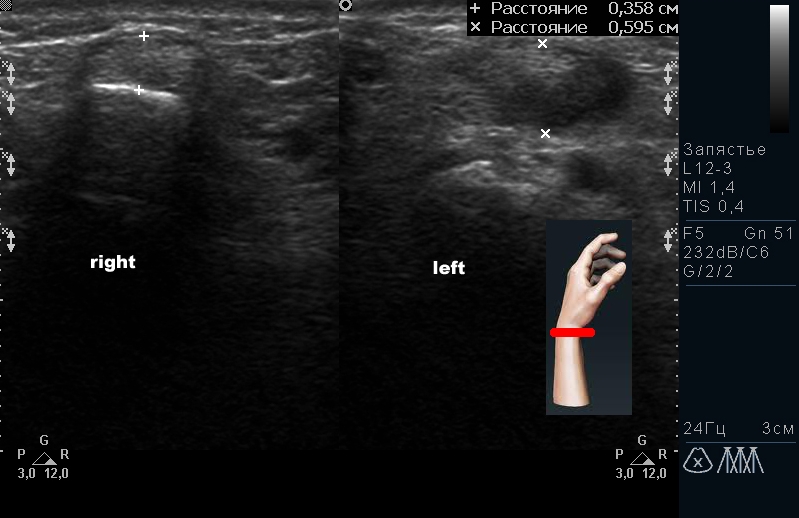

| Синдром запястного канала | Сдавление срединного нерва, отек тканей в карпальном канале | Неинвазивный метод оценки состояния срединного нерва |

- Запястный синдром (туннельный синдром). Основной симптом — потеря чувствительности в пальцах, связанная с сжатием срединного нерва запястья сухожилиями и костями. УЗИ позволяет хорошо визуализировать это состояние. В некоторых случаях для лечения применяются операции по освобождению кистевой связки.